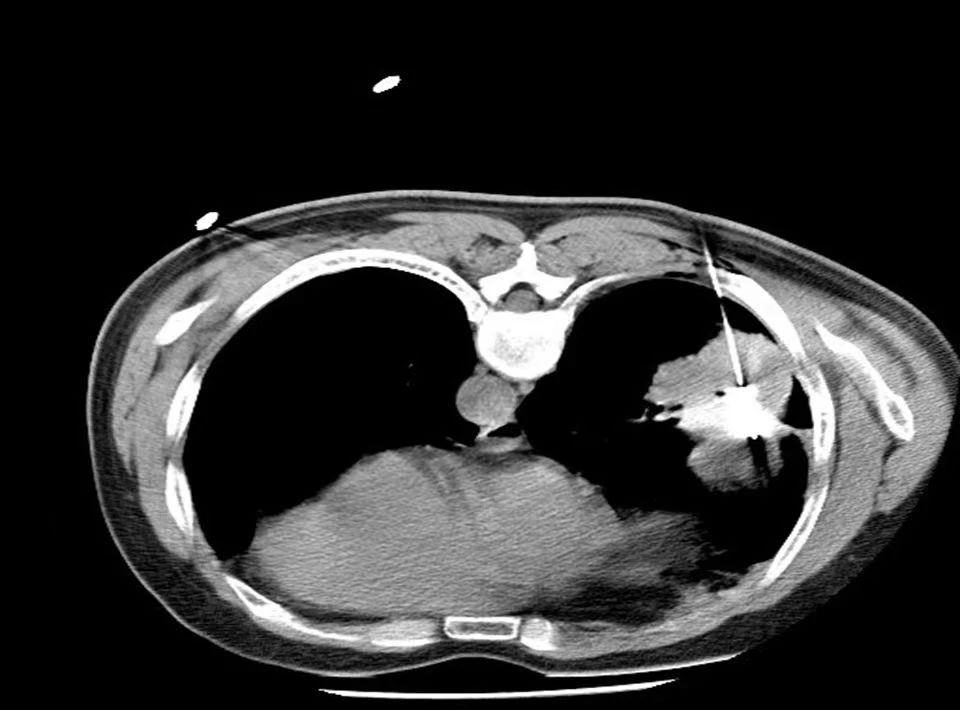

徐州市中醫(yī)院胸外科術前和放射科同事們一起為張大爺詳細規(guī)劃進針路線,術中對病灶進行精準穿刺,成功避開重要血管和器官。使用功率50w3分鐘消融腫瘤,同步活檢取病理;后續(xù)使用功率40w2分鐘進行腫瘤消融,術后影像顯示消融范圍全部覆蓋腫瘤病灶。整個微波消融手術全程耗時約半小時左右。